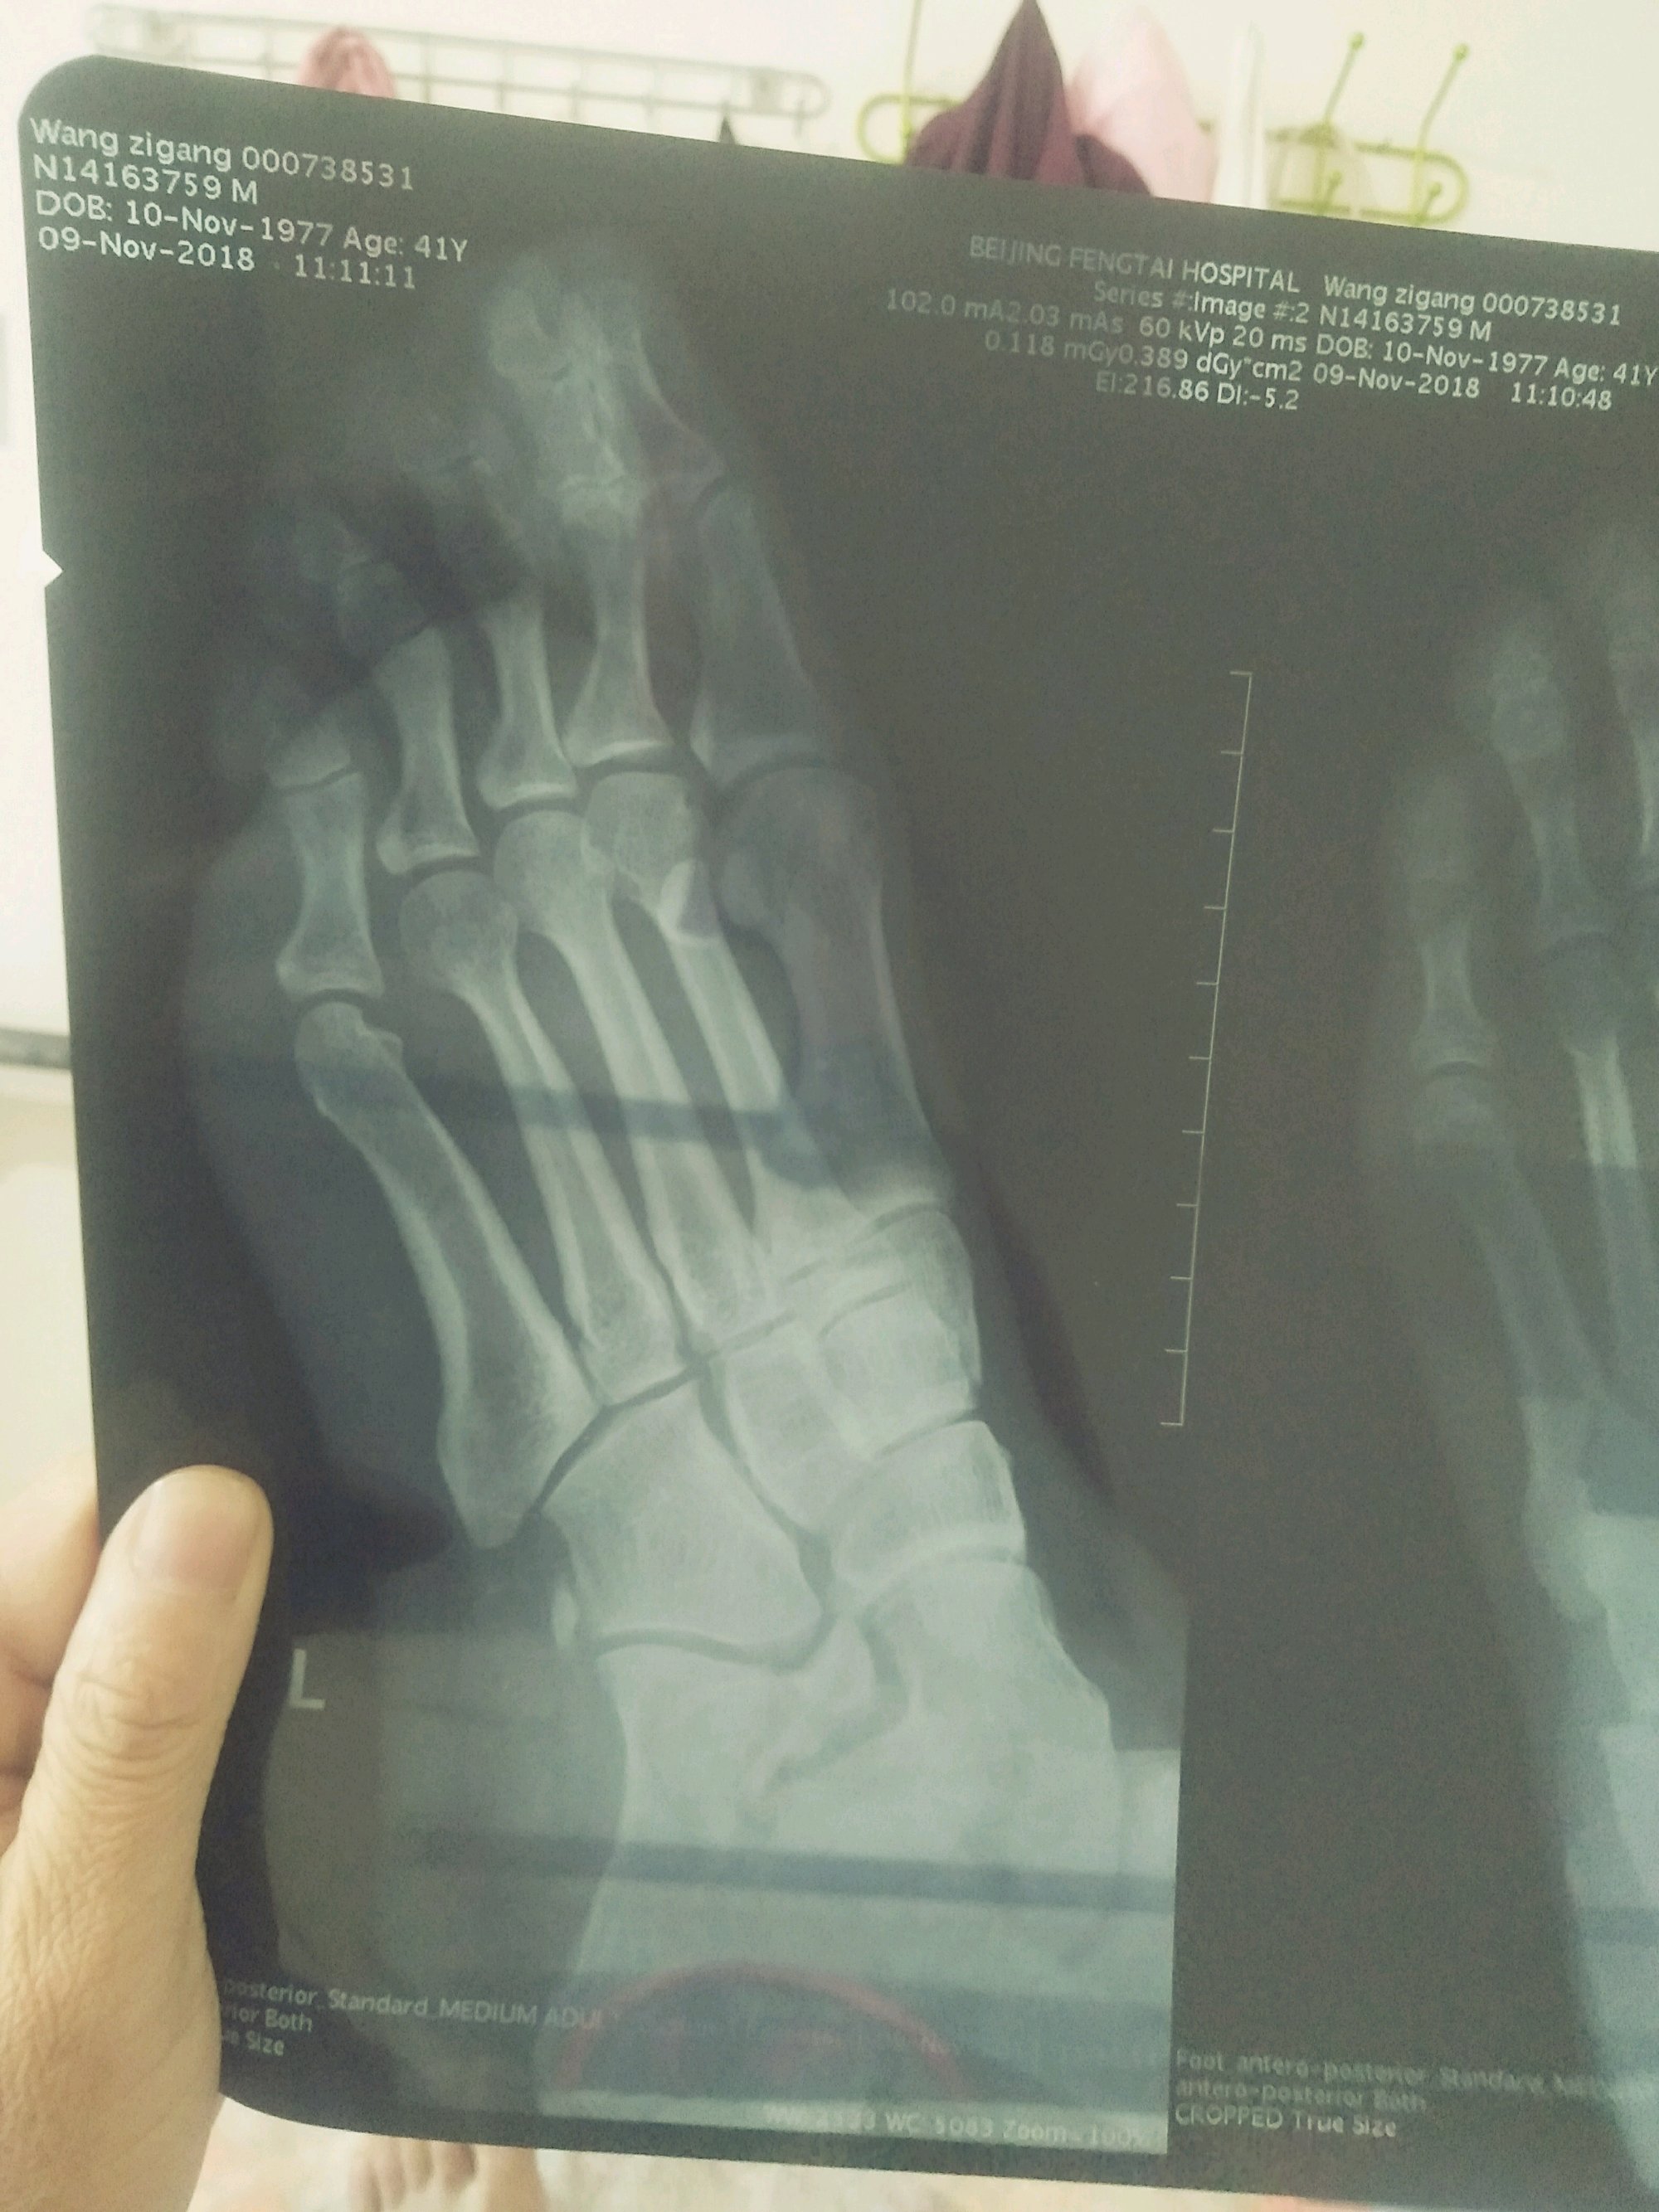

帮我看看这三这片子是怎么回事儿?我看不出来

脚背上的骨关节是不是移位了,跟骨距骨附骨有点骨裂吧

医生说是跟骨的 轴围的关节面骨折。

这个是怎么受伤的呢,这是横向冲击受伤的吗,

下楼梯歪脚。

哦,看见了,对对,是骨折了,这个可以保守的,

保守治疗两周骨折不连续才做的手术。